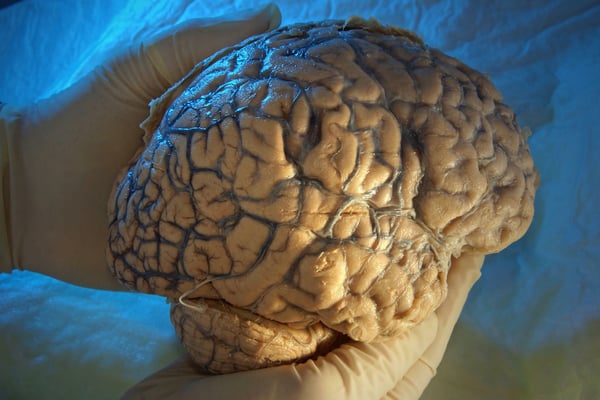

Der Mensch nutzt nur einen Bruchteil seines Gehirns

Zwar keine Ernährungsweisheit, aber ein Gesundheitsmythos ist, dass der Mensch gar nicht die volle Leistung des Gehirns ausschöpfe. Einmal heißt es 10 Prozent, ein andermal 25 Prozent. Mehr unserer Hirnkapazitäten nutzen wir nicht? Doch, tatsächlich nutzt der Mensch alle Bereiche seines Gehirns. Untersuchungen haben gezeigt, dass es keine inaktiven Teile gibt. So verführerisch der Gedanke an noch ungenutzte Areale und Möglichkeiten wie Telepathie und Telekinese sein mag, sie bleiben Fantasterei.

>> Hier finden Sie weitere spannende Mythen rund um unser Gehirn.